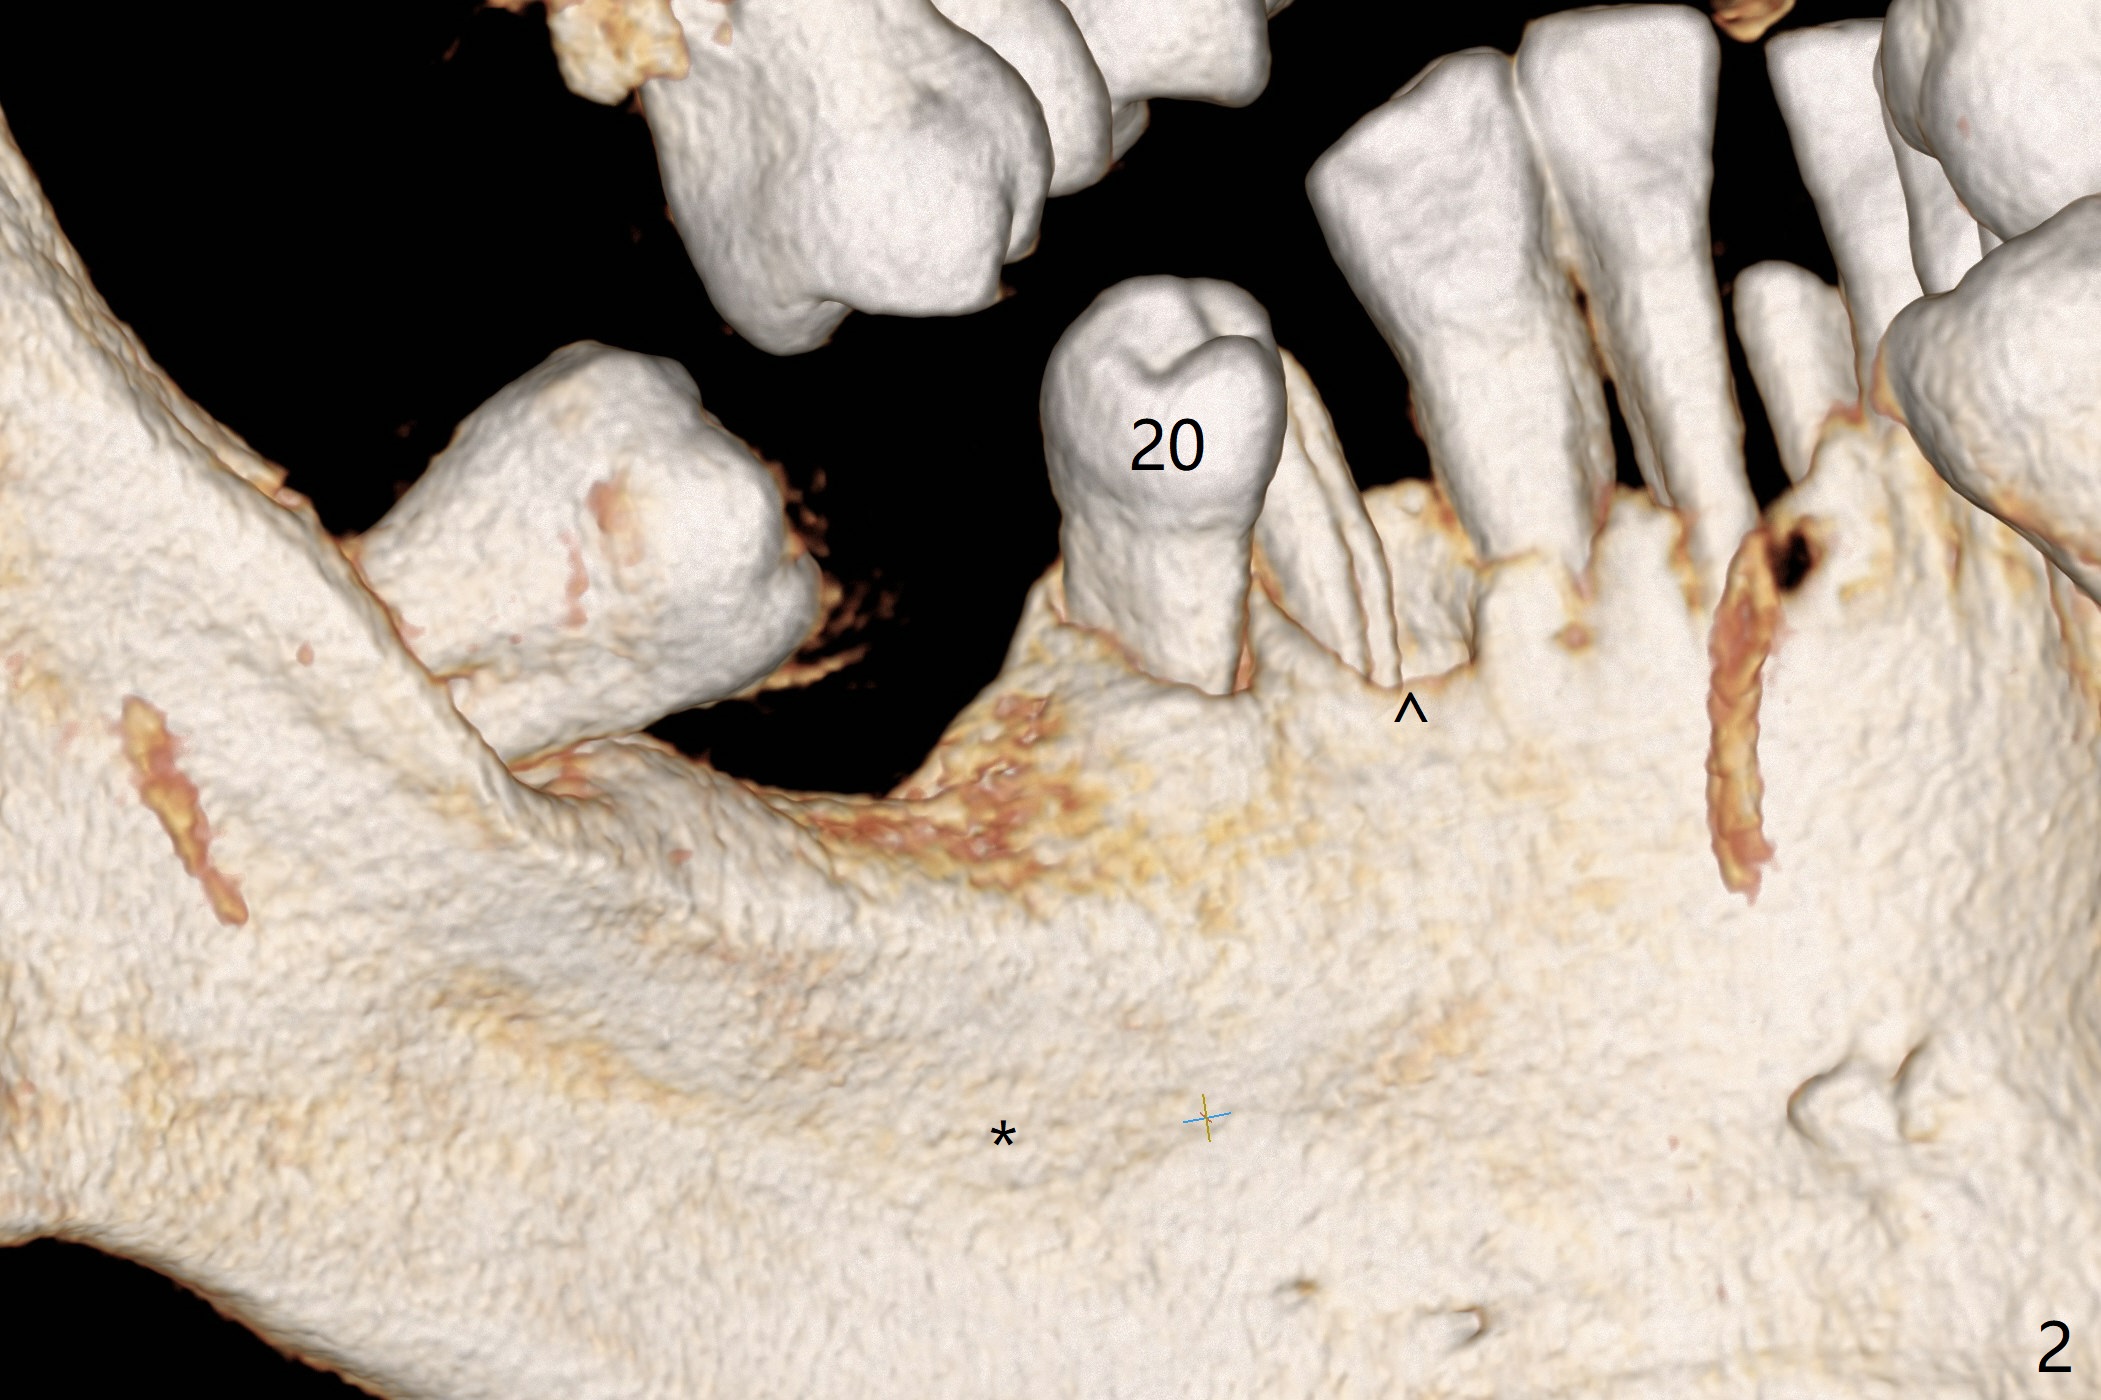

A 54-year-old man has poor dentition, including missing tooth of #19 and residual root at #20 (Fig.1). The lingual crest (Fig.2 (lingual view), Fig.4 (L)) is lower than the buccal one. The Inferior Alveolar Canal (Fig.3 IAC) becomes the Incisive Canal (IC, Fig.4 red circle) after the Mental Loop (Foramen). An implant at #21 will be placed at the level between the buccal and lingual crests (Fig.4) with osteotomy initiated in the middle of the socket. Bone graft is to be placed around the coronal end of the implant (yellow circles).

The socket at #19 appears to have not completely ossified (Fig.1 *, Fig.5). Use Magic Split and Magic Expanders to expand the ridge top so that an implant will be placed higher for favorable crown/implant ratio (reduce abutment screw loosening). Note the concavity at the site of #19 while osteotomy (Fig.2 *).